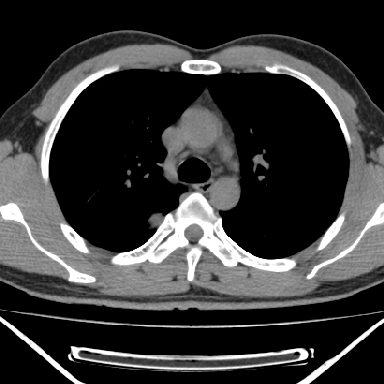

m 30 右胸痛10年

右上后纵隔脊柱旁类圆形肿块,边界光整,与胸腔呈钝角,首先考虑来源于肺外,神经源性肿瘤(神经鞘瘤可能大,神经鞘瘤)

病灶与椎间孔间存在脂间隙,病灶较大,椎间无明显异常改变,与胸膜移行处可见尾状影,考虑胸膜肿瘤,以良性间皮瘤可能性大

病灶最大径线处于肋间隙,不排除起源于肋神经源性肿瘤

m,30岁,右胸痛10年。

右上后纵隔旁软组织肿块影,与肺界面光滑,与胸壁呈钝角相交,提示肺外病变。位于肋骨下缘,边缘清楚,呈三角样指向与右侧椎间孔,但并示进入椎间孔;与对侧神经根对比,属同一走行方向。

考虑后纵膈良性肿瘤,神经源性肿瘤可能大。

鉴别:胸膜来源肿瘤。影像表现虽有肺外征象,但无胸水等相应佐证;再者,病史前10年,超长,与胸膜肿瘤不太吻合。

建议:再次查体,问清疼痛部位,如为1~2个肋间痛则神经源性肿瘤可能大,如疼痛较弥散,不按肋间分布,则可能为后纵膈其它来源肿瘤。

右上后纵隔脊柱旁类圆形肿块,边界光整,与胸腔呈钝角,首先考虑来源于纵膈,神经源性肿瘤可能大。

右上后纵隔脊柱旁见长椭圆形肿块,边界光整,与胸壁呈钝角。周围骨质未见异常。

考虑、1、后纵隔神经源性肿瘤;

2、不除外单发胸膜间皮瘤。